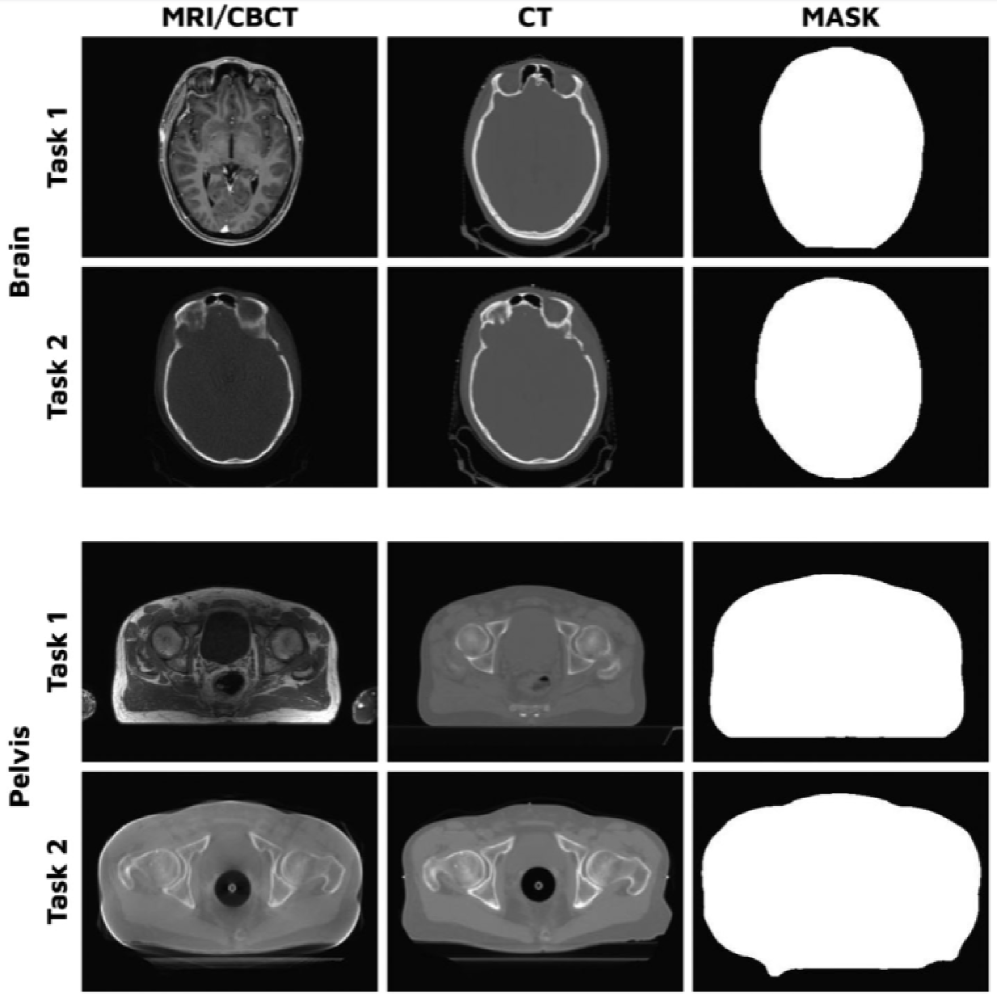

SynthRAD2023

SynthRAD2023 is a synthetic radiology dataset designed for cross-modal brain image reconstruction tasks. It contains paired Computed Tomography (CT) and Magnetic Resonance Imaging (MRI) volumes with various degrees of sparsity and anatomical variability. The dataset simulates realistic clinical conditions by incorporating sparse CT slices and multiple MRI modalities, facilitating the evaluation of reconstruction methods under challenging sparse input scenarios. Figure 8 shows example images from the dataset. The images are reproduced from the original paper.